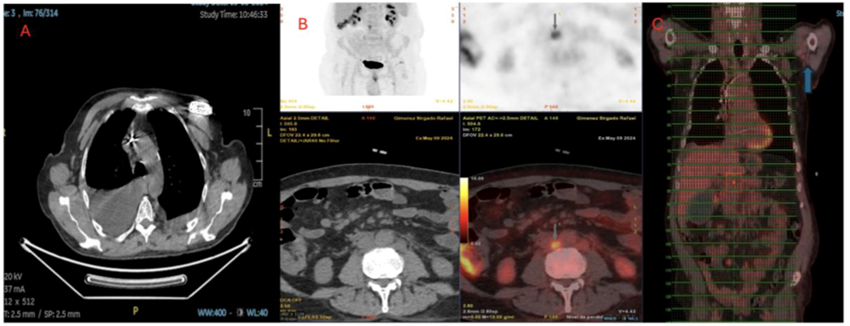

The PET-CT scan showed supra- and infradiaphragmatic lymphadenopathy, hypermetabolic thyroid lesions, and a left axillary lymph node with significant uptake (Figure 3). Colonoscopy revealed only diverticulosis. Lymphoscintigraphy of the upper and lower limbs was normal (Figure 4). Cytometry of the pleural fluid showed a predominance of T lymphocytes, and the peripheral blood smear showed no abnormalities.

Figure 3: PET-CT. A) Axial view of the lung window reveals the presence of a larger and more extensive pleural effusion on the right side, with no metabolic activity. B) Axial view of the abdomen window reveals several lymph nodes, notable for their size and metabolism, located in the inter-aortocaval area. C) Significant metabolic uptake at the level of the left axillary lymph node.